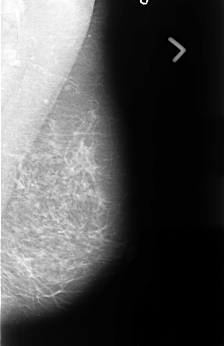

B_3441_1.LEFT_MLO

LEFT_MLO LINES 4488 PIXELS_PER_LINE 2912 BITS_PER_PIXEL 12 RESOLUTION 50 NON_OVERLAY